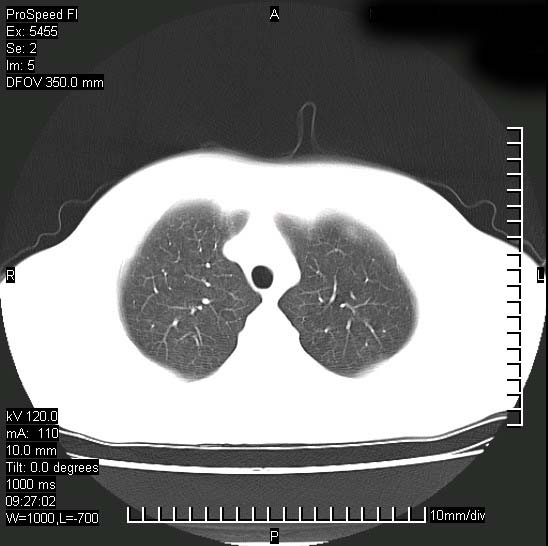

以下是引用zjzjr在2008-12-3 20:50:00的发言:[br]考虑泛细支气管肺炎,建议进一步检查除外肺出血性疾病如含铁血黄素沉着症、肺肾综合征等。

以下是引用zjzjr在2008-12-3 20:50:00的发言:[br]考虑泛细支气管肺炎,建议进一步检查除外肺出血性疾病如含铁血黄素沉着症、肺肾综合征等。

以下是引用光线在2008-12-3 20:19:00的发言:[br]双肺间质性改变。